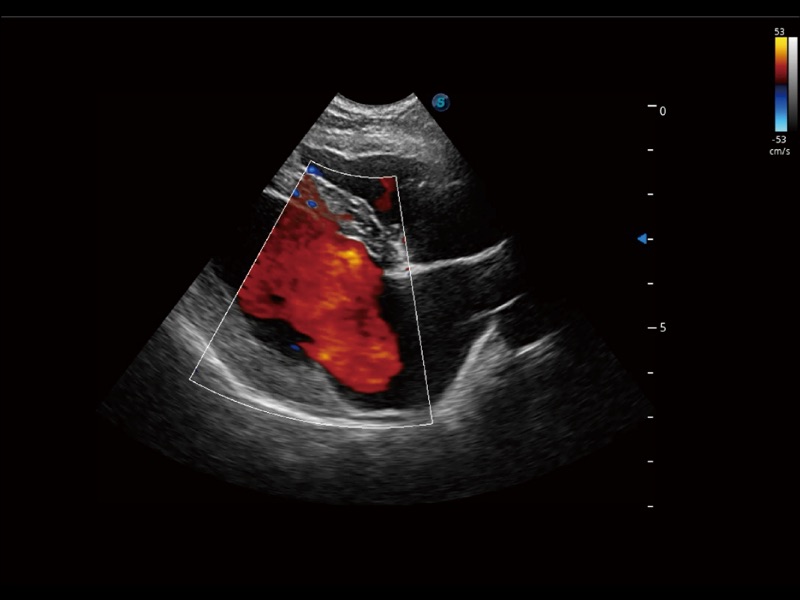

• Micro F 显微血流成像

通过创新的 Matrix E自适应滤波器和超长时间域算法,极大提升超低速微细血流的检出能力,同时更精准地滤除软组织和噪声信号,为兽用医生提供以往无法通过常规血流获得的疾病诊断信息。

• 宽景成像

通过色彩血流和实时宽景相结合,可观察到完整的静脉或动脉的血流,方便医生检查。实时扫查过程中,如有任何操作失误也可以很容易地进行回扫擦除,而不会中断扫查。

(犬)肾脏显微血流

(犬)髂动脉血流